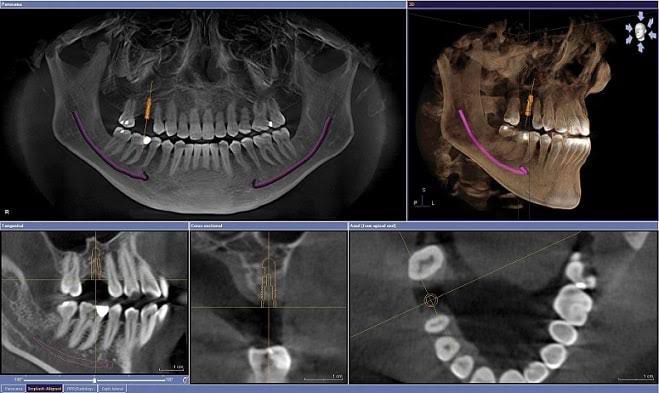

Estudio 3D para implantología

Esencial para la planificación de implantes, ya que proporciona imágenes tridimensionales detalladas que ayudan a los odontólogos a evaluar la estructura ósea y a planificar el procedimiento con precisión.